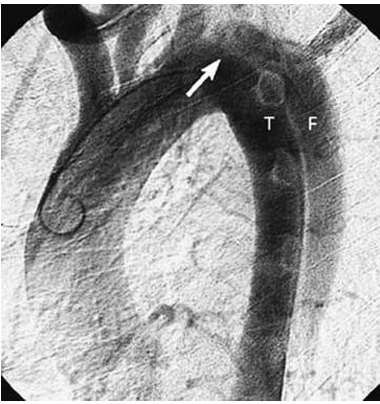

“A morte por dissecação da aorta torácica geralmente é causada por regurgitação aórtica aguda, obstrução de importante ramo, tamponamento pericárdico ou ruptura da aorta. As complicações decorrentes da dissecção da aorta torácica podem ocorrer no tórax ou em localização extratorácica. Mais de um terço dos pacientes com dissecção aórtica apresentam sinais e sintomas secundários ao envolvimento de outros sistemas de órgãos. O mecanismo mais comum é o desenvolvimento de isquemia secundária à obstrução de artérias ramificadas com origem na aorta, como as artérias renais. A obstrução do ramo-vaso pode ser causada por uma extensão do processo de dissecção na parede do vaso ou uma compressão direta da artéria ramo por um lúmen falso em expansão”. A imagem que segue demostra essas e outras regiões. Escolha a opção que revela a função/fisiologia da artéria aorta.